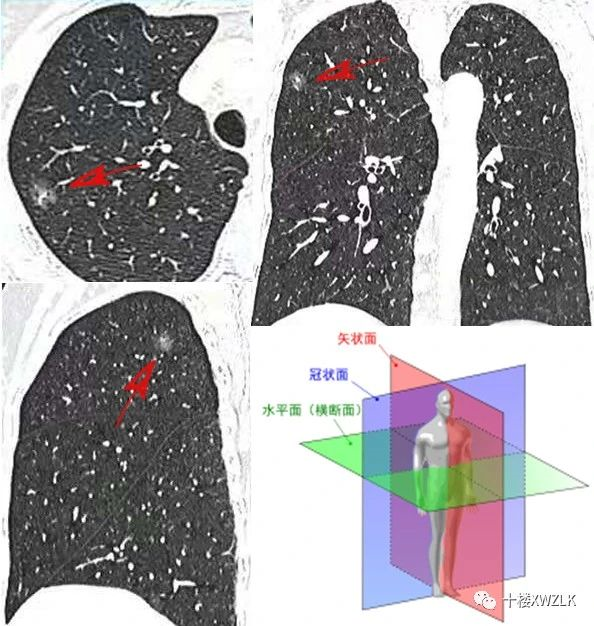

手把手教会你读懂肺部ct-肺部影像学检查概述及ct读片

肺部ct怎么看图解

肺部ct怎么看图解解读